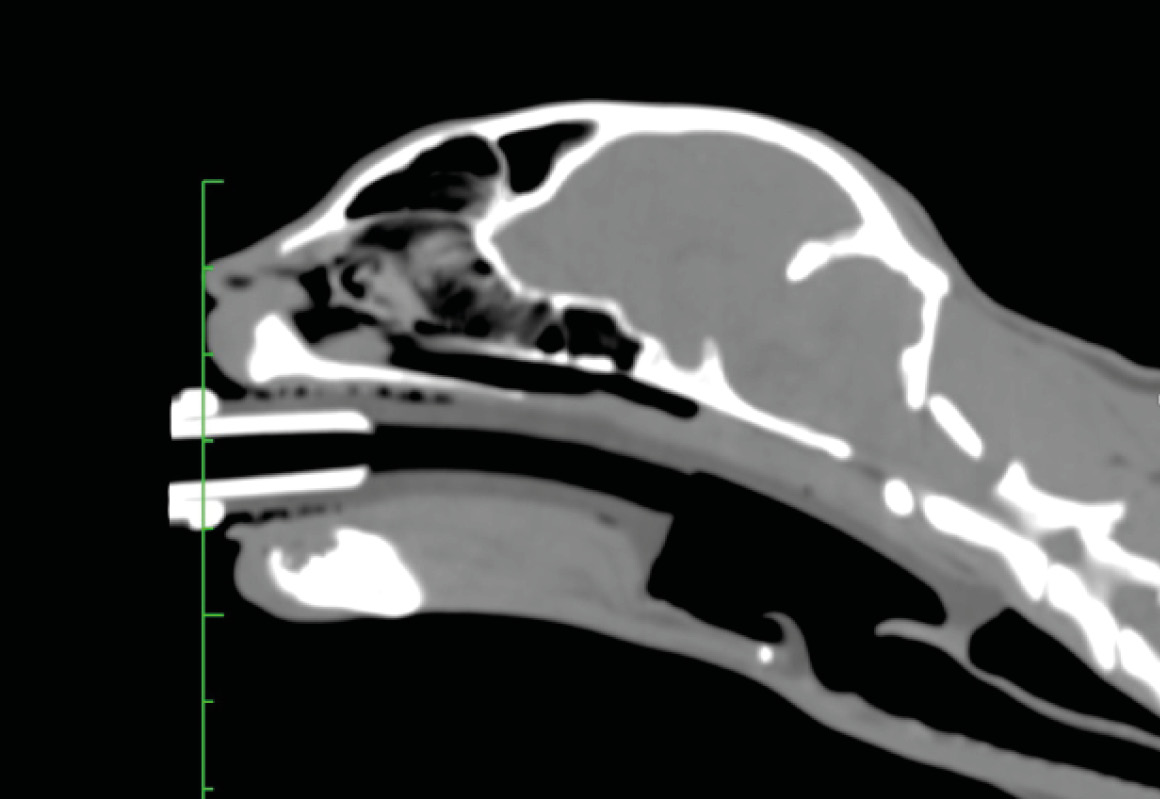

Su colocación es fácil, ya que solo requiere abrir la boca del animal, estirar la lengua e introducir el dispositivo lubricado hasta que está colocado sobre la entrada de la tráquea (imagen 4). La cúpula queda por encima de las estructuras laríngeas, por lo que, en principio, estas no sufren traumatismo (imagen 5). Para estar seguros de que la colocación es correcta, debemos usar el capnógrafo y observar una curva de capnografía perfecta.

- Gómez-Silvestre, J. M., García-Fernández, A., Redondo, J. I., Marti-Scharhausen, M. D. L. R., Cañón, A., Hernández, E. Z., Viscasillas, J: Computed Tomography assessment of V-Gel Advanced supraglottic airway device placement in cats. Vet Anaesth Analg. 2025, in press

- Debuigne M, Gatel L, Chesnel M: Placement of the feline V-gel Advanced supraglottic airway device and tracheal selectivity during controlled mechanical ventilation: a clinical and tomodensitometric evaluation. J Feline Med Surg. 2024; 26(9):1098612X241264725.